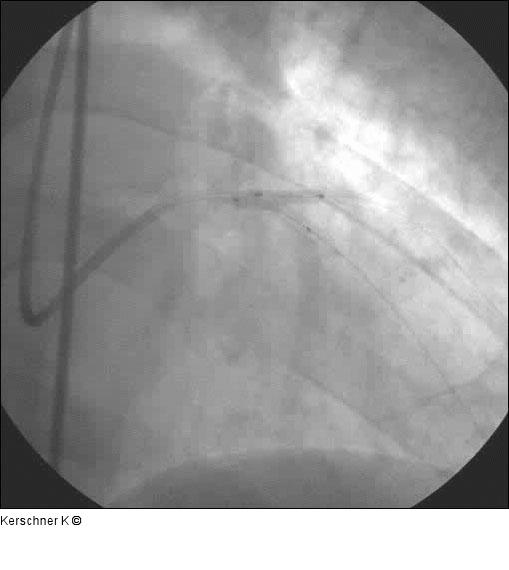

Abbildung 10: Kissing-Ballon Kissing Ballon R. diagonalis mit 2,5 / 15 mm Ballon und LAD 3,0 / 15 mm-Ballon mit jeweils 12 atm nach vorheriger isolierter Dilatation Abgang R. diagonalis mit 1,5- und 2,5-Ballon mit 20 atm. |

Kissing Ballon R. diagonalis mit 2,5 / 15 mm Ballon und LAD 3,0 / 15 mm-Ballon mit jeweils 12 atm nach vorheriger isolierter Dilatation Abgang R. diagonalis mit 1,5- und 2,5-Ballon mit 20 atm. |